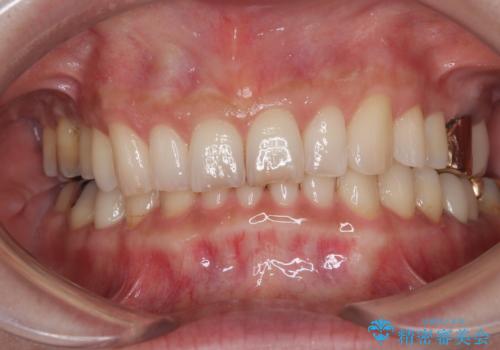

処置後はオールセラミックブリッジにて補綴し、再発防止のために就寝時にナイトガード(マウスピース)を装着していただくこととしました。

術後に痛みの続く処置を2度も受けていただくこととなりましたが、処置後は出血などの気になる症状がなくなり、患者様には大変満足していただきました。